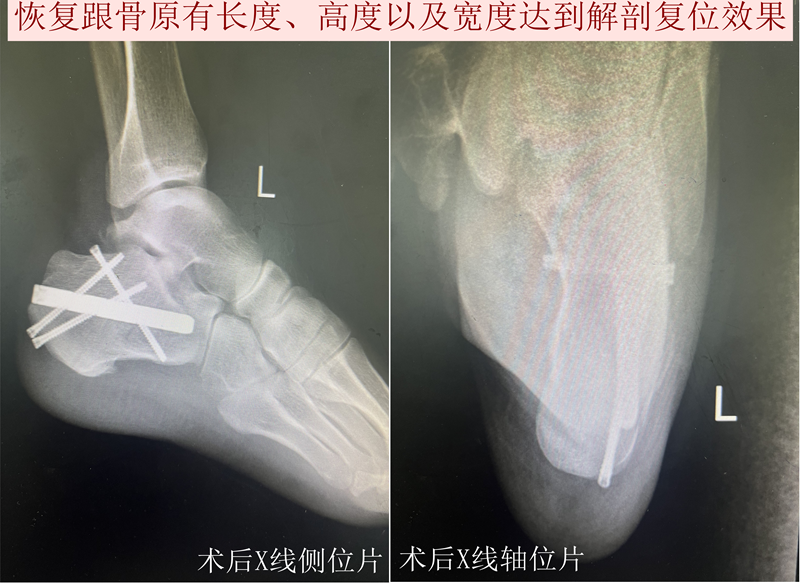

与传统方案不同,跟骨交锁髓内钉技术代表了一种全新的“内固定”理念。该技术仅需在跟骨结节下方(脚后跟处)切开一个约1厘米的小切口,将一枚特制的髓内钉主钉置入跟骨内部的骨髓腔中。通过主钉远端的多向交锁螺钉,可以牢牢“抓住”碎裂的跟骨前部和关节面骨块;近端的交锁螺钉则能提供强大的稳定性,有效恢复跟骨的高度、宽度和关节面的平整,整个过程对周围软组织的损伤降到了最低。

跟骨交锁髓内钉技术尤其适用于Sanders II型、III型及部分跟骨关节内骨折、舌型骨折和跟骨结节骨折等。其成功应用体现了现代骨科手术向微创化、精准化、智能化发展的必然趋势。